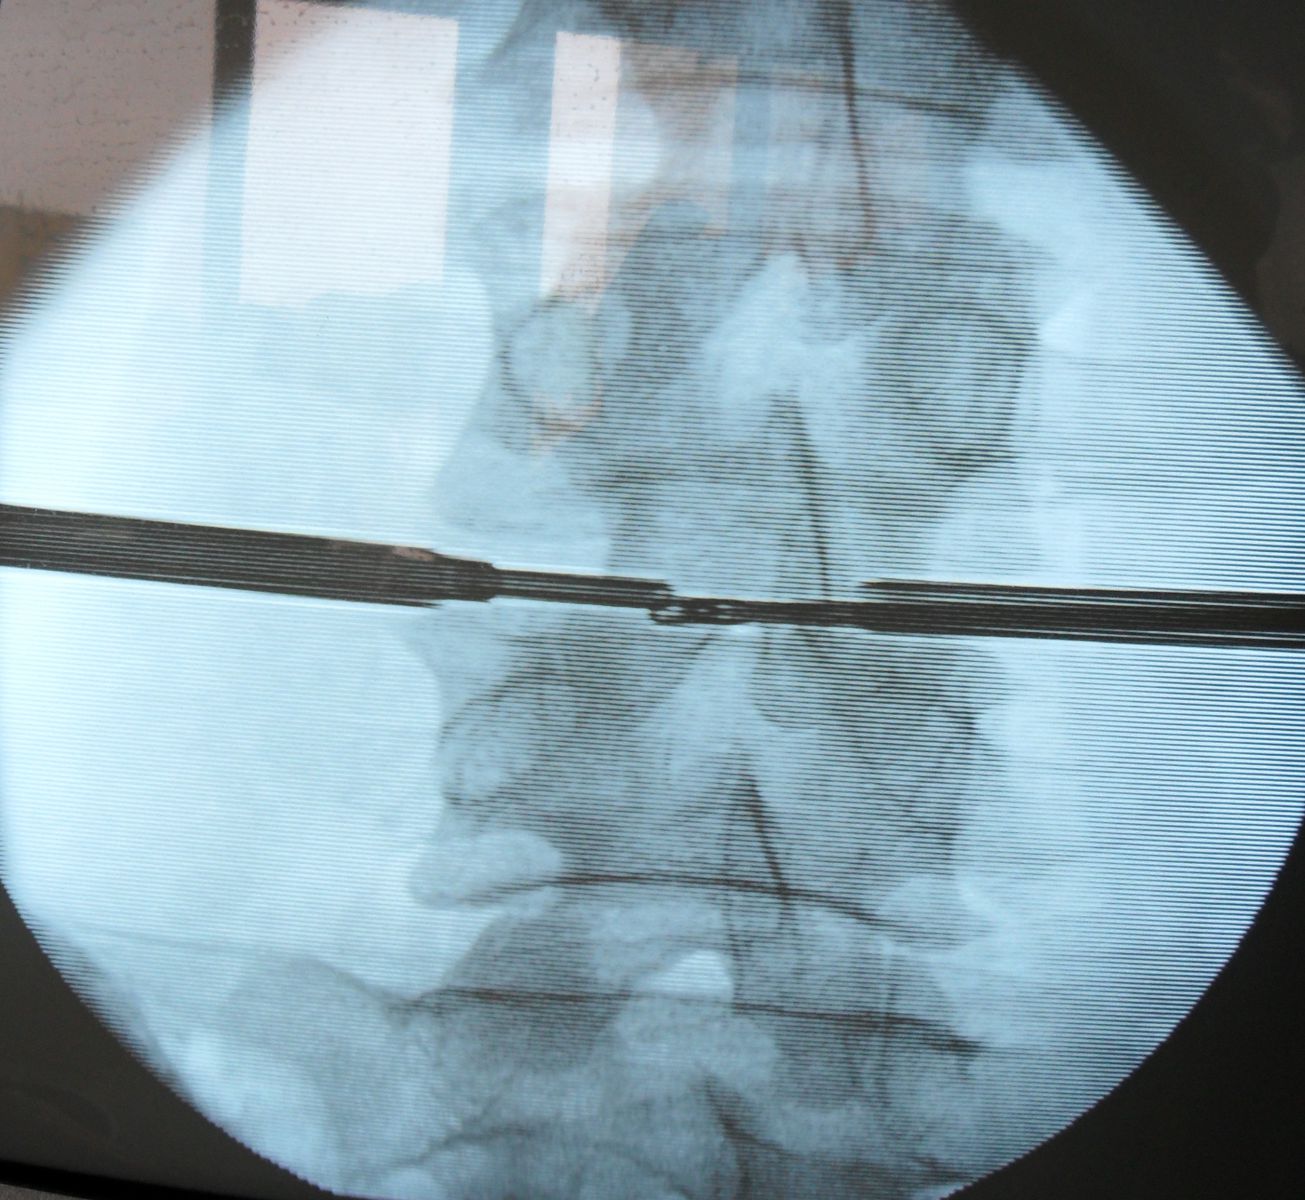

- Биопсия - необходимо постараться получить прямые посевы из диска или тела позвонка на пораженном уровне. Возможно выполнение как чрезкожной биопсии под местной анестезией, так и получение биопсии в ходе отрытой операции. Выбор оптимальной тактики осуществляет Ваш нейрохирург.

- Неясный диагноз, особенно если есть серьезное подозрение на опухоль, возможно выполнение чрезкожной биопсии иглой под контролем рентгена или открытая биопсия.

- позволяет верифицировать диагноз остеомиелита позвоночника;

- выделить и установить чувствительность возбудителей к антибактериальным препаратам;

- позволяет проводить антибактериальную терапию через систему дренаж-ирригатор непосредственно в очаг воспаления.

В клинике применяется широкий спектр хирургического лечения (открытая санация и дренирование патологического очага, современные малоинвазивные хирургические методики - операция выполняется через прокол в коже под местным обезболиванием) и различные стабилизирующие операции с применением титановых транспедикулярных конструкций.